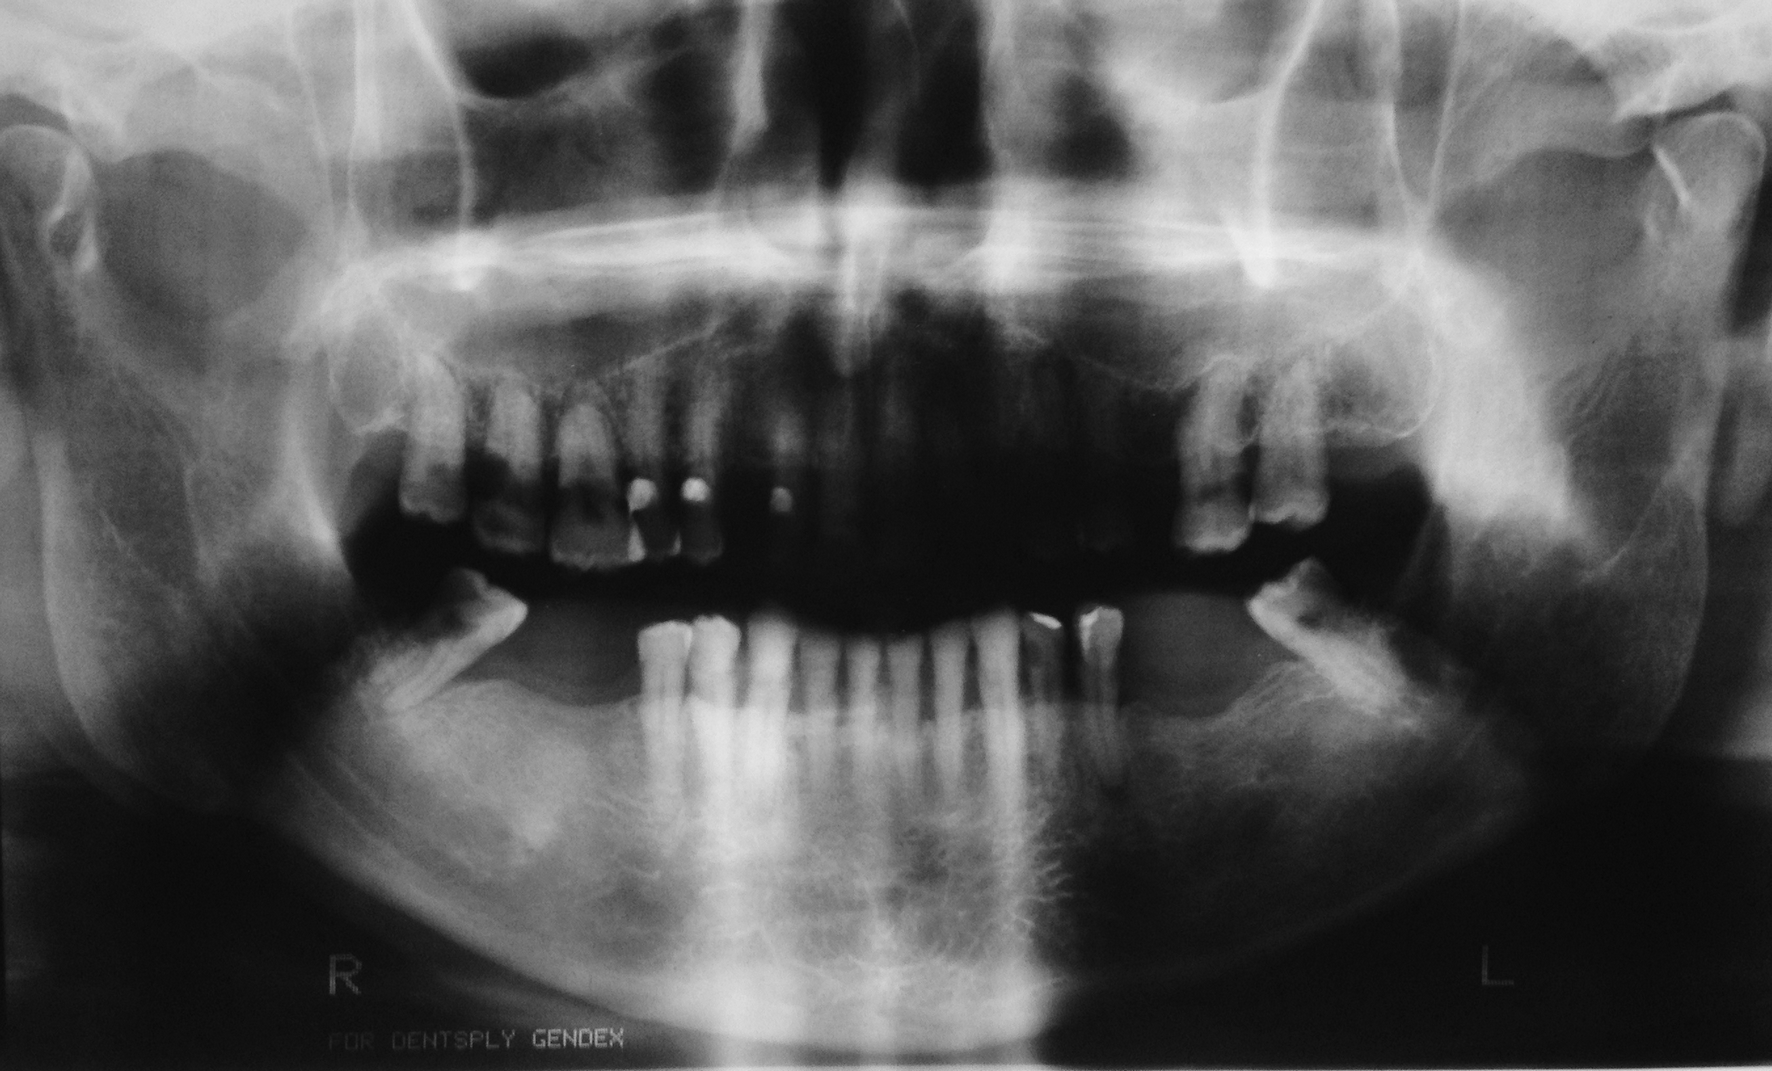

Osteoradionecrosis (ORN) is one of the most severe oral complications after the head and neck cancer treatment. Tooth extraction, through its traumatic stimulation, is identified as an important predisposing factor. Indications and preventive methods for carrying out these procedures in irradiated patients are questioned, thus, establishing appropriate protocols is essential. This article reports a case of multiple tooth extractions in a cancer patient whose preventive measures were taken without the occurrence of complications. Based on a literature review, this paper accounts the appropriate indications of this procedure, the risk of developing osteoradionecrosis, and the prevention possibilities for this sequela. In addition, this report addresses a viable oral rehabilitation alternative after this kind of surgery by using overdenture on the lower jaw teeth.